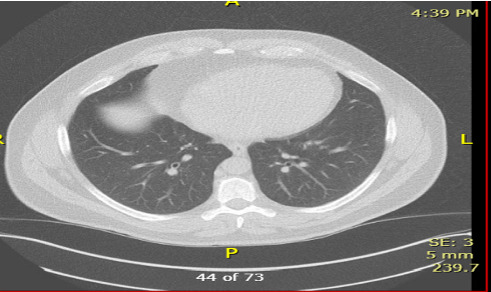

肾细胞癌(RCC)的幸存者,特别是肾切除术后,需要长期随访复发或全身并发症。当有肾细胞癌病史的患者出现肺结节时,我们必须考虑到感染性疾病,特别是那些环境暴露和与肾切除术后继发代谢变化相关的免疫改变的患者。我们报告了一位49岁男性患者,他在肾切除术后患有肾小细胞癌,有长期吸烟史,并有明显的煤尘暴露史,他发展为进行性肺结节。虽然最初怀疑为转移性肾细胞癌(mRCC),但连续影像学显示结节增大,PET扫描无代谢活动,需要进一步评估。鉴于持续的呼吸道症状,他接受了支气管镜检查并进行了微生物学分析,发现了烟熏曲霉,最终被诊断为慢性肺曲霉病。我们的患者成功地用伏立康唑治疗,并随着时间的推移显示出显著的临床改善。在本例中,我们观察了RCC幸存者肺结节的诊断困境,以及广泛鉴别以避免误诊的重要性。肾切除术后的免疫变化,可能伴有慢性肾脏疾病(CKD),或长期的肿瘤监测可能使患者处于机会性感染的危险之中。为了确保及时发现和治疗可能模拟肿瘤进展的感染,临床医生治疗RCC幸存者应将微生物学诊断纳入常规肺部评估。

Survivors of renal cell carcinoma (RCC), especially following nephrectomy, require long follow-up for recurrence or systemic complications. While those with a history of RCC develop pulmonary nodules often with concern for metastasis, we must consider infectious diseases, especially in patients with environmental exposures and immune alterations related to metabolic changes secondary to nephrectomy. We report a 49-year-old male with a history of RCC status postnephrectomy, history of long-term smoking, and history of significant coal dust exposure, who developed progressive pulmonary nodules. Although initially suspected to be metastatic RCC (mRCC), serial imaging demonstrated nodule enlargement without metabolic activity on PET scan, requiring further evaluation. Given the persistent respiratory symptoms, he underwent bronchoscopy with microbiologic analysis which identified Aspergillus fumigates and was ultimately diagnosed with chronic pulmonary aspergillosis. Our patient was successfully treated with voriconazole and over time demonstrated significant clinical improvement. In this case, we have made the observation of the diagnostic dilemma presented by the pulmonary nodules in RCC survivors and the importance of a broad differential to avoid misdiagnosis. Immune changes following nephrectomy, possible accompanying chronic kidney disease (CKD), or prolonged oncologic surveillance could place patients at risk for opportunistic infections. In order to ensure timely detection and treatment of infections that may mimic tumor progression, clinicians treating RCC survivors should integrate microbiologic diagnostics into routine pulmonary evaluations.